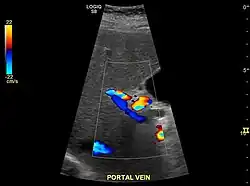

Imaging

Ultrasound is routinely used in the evaluation of cirrhosis.[45] It may show a small and shrunken liver in advanced disease. On ultrasound, there is increased echogenicity with irregular appearing areas.[64] Other suggestive findings are an enlarged caudate lobe, liver surface nodularity[65] widening of the fissures and enlargement of the spleen.[66] An enlarged spleen, which normally measures less than 11–12 cm (4.3–4.7 in) in adults, may suggest underlying portal hypertension.[67] Ultrasound may also screen for hepatocellular carcinoma and portal hypertension.[45] This is done by assessing flow in the hepatic vein.[68] An increased portal vein pulsatility may be seen. However, this may be a sign of elevated right atrial pressure.[69] Portal vein pulsatility is usually measured by a pulsatility index (PI).[68] A number above a certain value indicates cirrhosis (see table below).